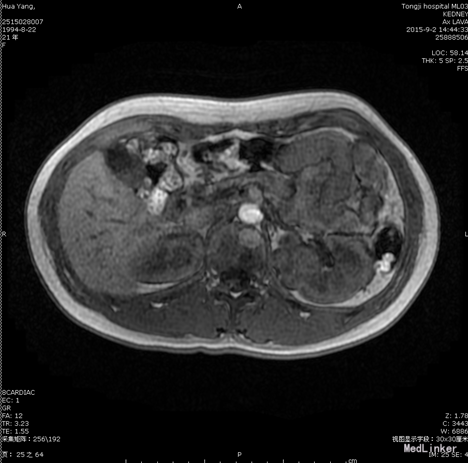

患者,女,21岁。 主诉:体检发现左肾占位4月余。 现病史:患者于患者约4月前单位行体检时发现左肾占位,在外曾于当地医院行CT检查提示“左肾良性肿块,不排除肾嗜酸细胞瘤可能”。

查体:T36.6℃,P84bpm,Bp104/66mmHg,双肾区叩痛阴性,外生殖器无畸形,双下肢无水肿。 辅助检查: 2015.9.15浠水县人民医院CT检查提示“左肾良性肿块,不排除肾嗜酸细胞瘤可能”。 2015.9.3我院MRI示“左肾占位,多考虑肿瘤性病变”。 双肾ECT检查示:双肾血流灌注、摄取功能大致正常,排泄通。

诊断:左肾肿瘤 处理:后腹腔镜下左肾部分切除术。以免疫治疗应用重组人白介素-2预防肿瘤的复发。